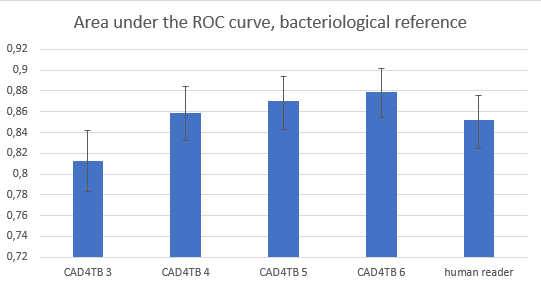

We also evaluated how accurate the software and the human observers are in determining if an X-ray is from a subject with bacteriologically confirmed TB. Here we used a validation data set of almost 2500 images, from 6 different sites in 6 different countries, and we had a culture or GeneXpert result for every case available. We found that CAD4TB 4 and CAD4TB 5 already outperformed human readers (85.9% and 87.0% versus 85.2% for the human readers). With CAD4TB 6 performance goes up a bit further, to 87.9%.

Figure 2. Performance of the new version of CAD4TB for predicting bacteriologically confirmed TB has further improved. It is outperforming human observers, but the difference is not statically significant.

One may wonder why the scores for the bacteriological reference are lower than for the radiological reference (both for CAD4TB and the human readers). The answer is that it is not always possible to detect TB on a chest X-ray (some TB patients have a normal chest radiograph), and on the other hand, some subjects have an X-ray with clear abnormalities suggestive of TB, but they are not bacteriologically positive. They may have another disease, or the X-ray shows signs of old and healed TB, or it may even be possible that the bacteriological reference standard is not correct.